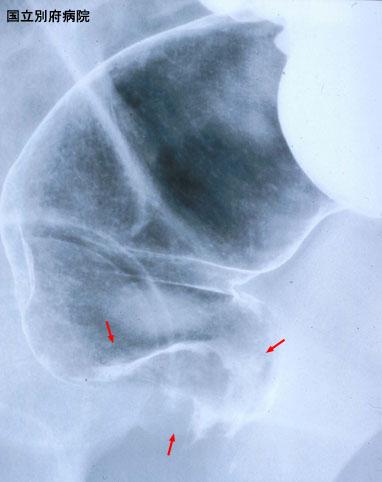

폐전이를 동반한 직장의 악성흑색종(증례제시:국립 벳부병원)

[Image-ID:3101]

질환(병리주체)의 분류

악성흑색종/

부위(장기별)

대장/직장

검사방법

X-P

종양의 육안분류

1형(종괴형)/

종양의 최대경(밀리미터)

40이상

종양의 심달도

ss(a1)